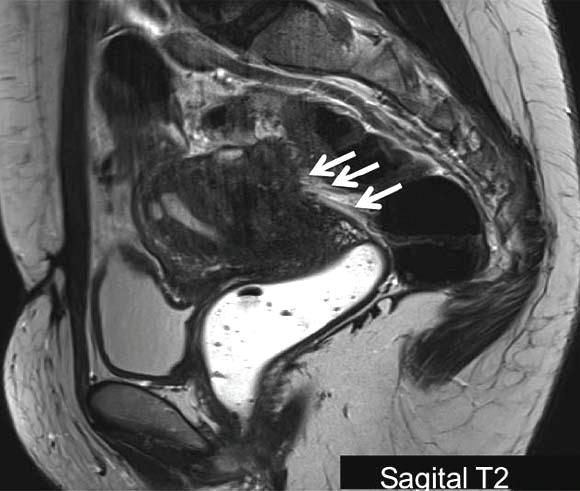

Se debe de sospechar cuando existen cólicos fuertes, relacionados o no al ciclo menstrual, cólicos que se recorren a las piernas, dolor durante las relaciones sexuales, molestias urinarias o rectales, fatiga, infertilidad, cuadros digestivos asociados al periodo menstrual entre otros. Durante la revisión con ultrasonido podemos, también, encontrar ciertos hallazgos, así mismo, en la exploración física. Una herramienta muy útil en la actualidad, es la resonancia magnética.

Un estudio de imagen normal, no descarta la existencia de endometriosis, es por esto que, anteriormente se consideraba a la cirugía laparoscópica como un estándar de oro para el diagnóstico. Sin embargo, no todas las pacientes son candidatas a cirugía, por tanto, es importante dar tratamiento médico de inicio, al sospechar, ya que puede mejorar mucho la calidad de vida y disminuir la extensión de la enfermedad.

“Mi papel en la clínica de endometriosis es el de dar un diagnóstico más preciso y específico de los endometriomas y una mejor caracterización de la endometriosis profunda, todo esto con el mapeo por estudio de resonancia magnética.

La resonancia es capaz de evaluar lesiones ocultas por densas adherencias, las cuales no son visibles en la laparoscopía. Es esencial que el radiólogo se encuentre familiarizado con los hallazgos de imagen de la endometriosis, a fin orientar y proporcionar información adecuada para el diagnóstico y tratamiento de esta patología.